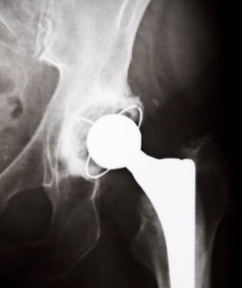

内布拉斯加大学医学中心和纽约特殊外科医院的Dong Wang及其同事解释说,关节置换术中的磨损会产生微小的碎屑,这些碎屑会引起局部炎症并导致骨质流失。发生这种情况时,植入物可能会松动并为失败做好准备。

他们指出,治疗通常来不及,因为很难在早期发现问题。科学家指出:“不幸的是,当报道疼痛或清晰的放射学证据时,已经发生了相当多的骨质流失,无法轻易恢复。”